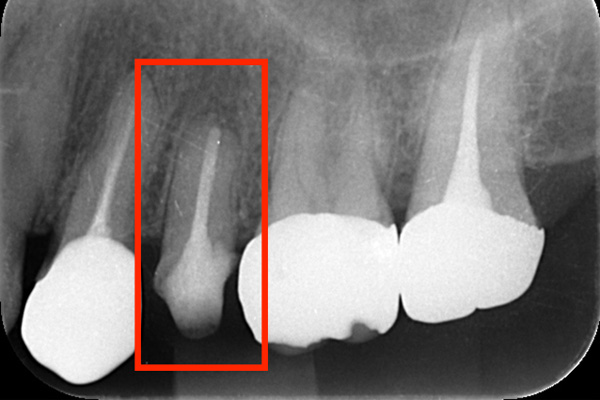

こちらは根の途中までしか防腐剤がはいってませんでした。患者様が違和感を訴えたため、治療を行いました。防腐剤を取り除き、根の中を清掃し、根の先端までしっかり防腐剤をいれました。

こちらは根の中の防腐剤が疎で、最近が繁殖するスペースをあたえてしまっていたため、患者様に違和感を感じさせていました。そこで、中の防腐剤を取り除き、それをCTとマイクロスコープで確認し、清掃を行い、今度は緊密に防腐剤を入れていきました。

根の先に膿が溜まっています。

根の中の清掃を行い、防腐剤を詰めました。

膿の塊がなくならないため、根の先を切り取りました。と同時に膿の塊も取り除きました。

1ヶ月後。根の先の膿がなくなったことと、根の先端を切り、感染物質がなくなったことで、骨の再生が始まっています。